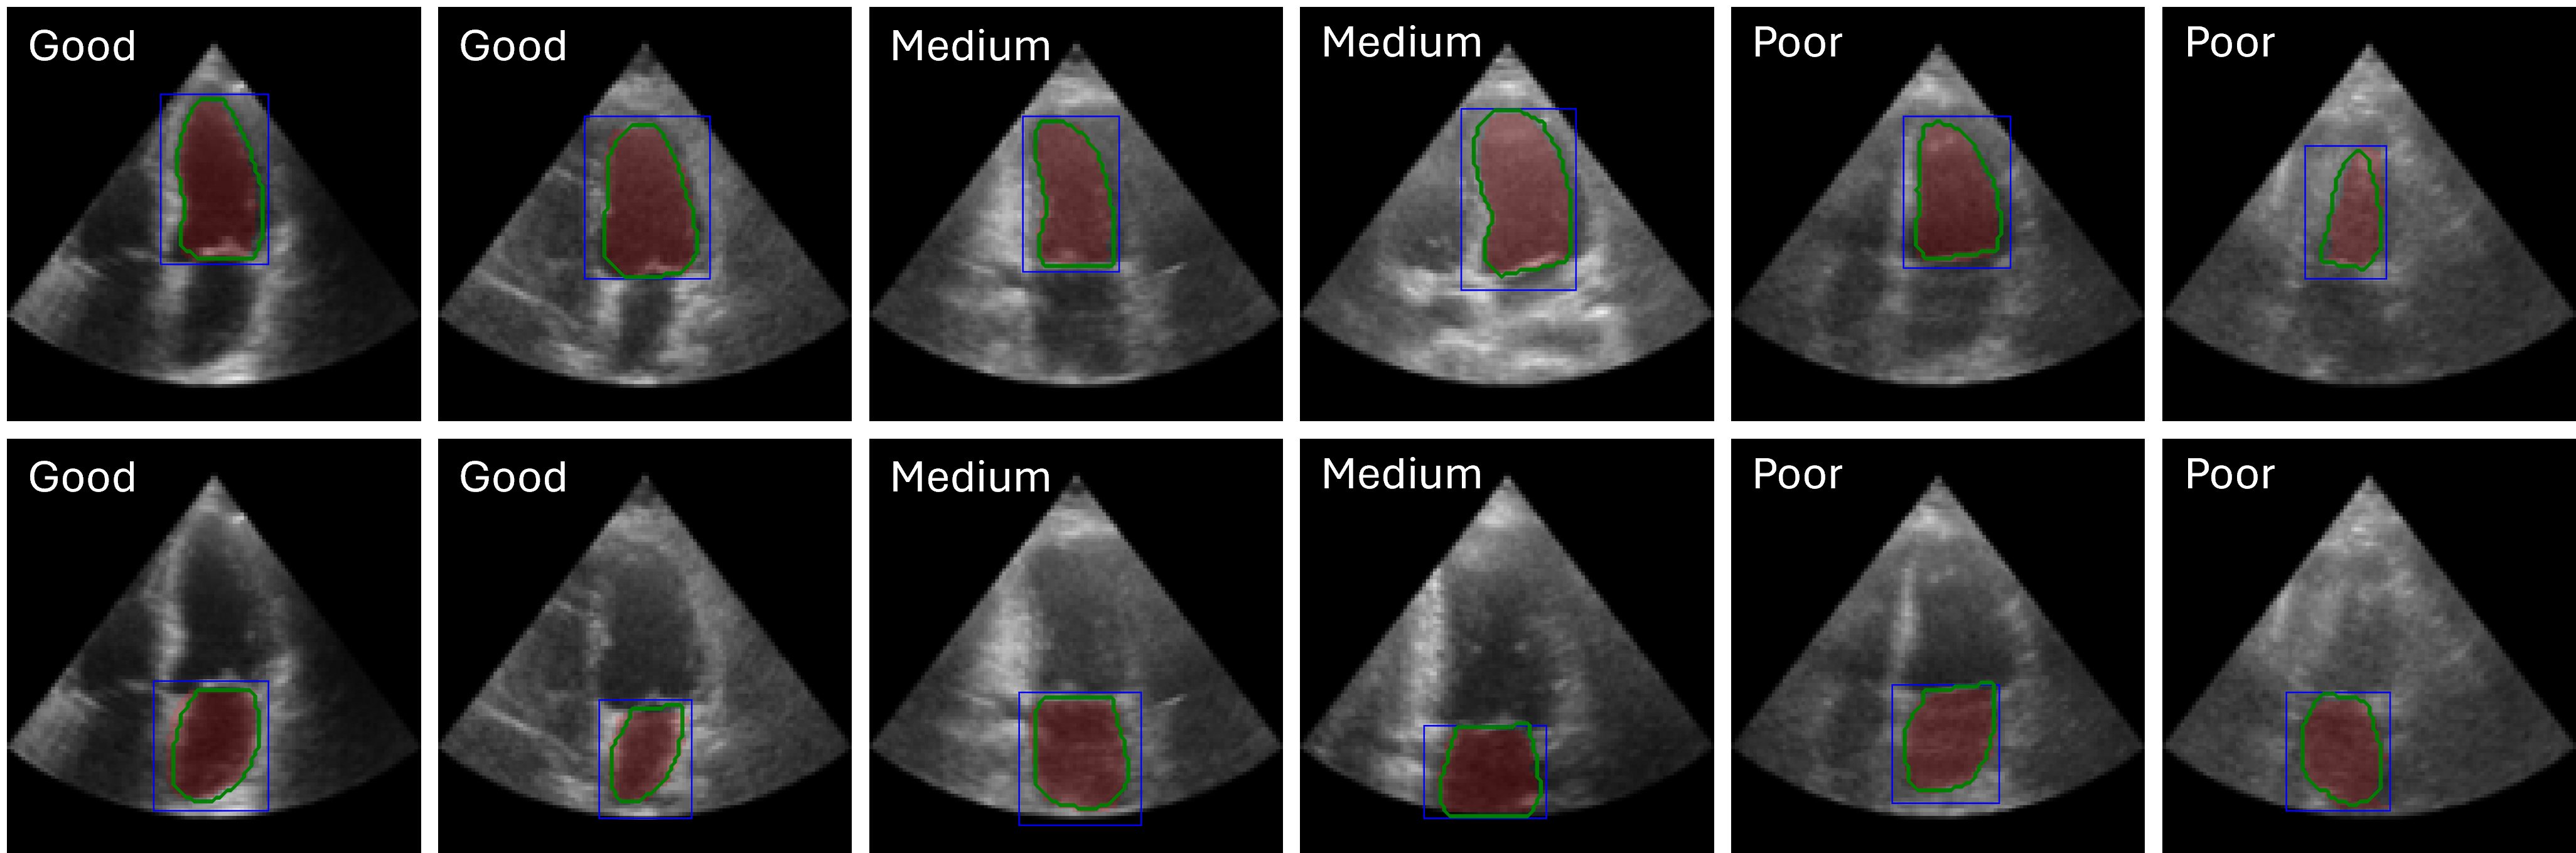

Interactive segmentation

We adapt EchoVLM for chamber segmentation tasks by attaching a prompt-based (box) encoder-decoder module following SAM (kirillov2023segment). Training and evaluation is conducted on three public benchmarks: EchoNet-Dynamic (left ventricle masks in A4C views) (ouyang2020echonetdynamic), EchoNet-Pediatric (left ventricle masks in A4C, PSAX views) (reddy2023video) and CAMUS (left ventricle and atrium masks in A2C views) (leclerc2019deep). We report Dice similarity coefficient (DSC) and compare with task-specific baselines (U-Net (ronneberger2015u) or Deeplabv3 (chen2017rethinking)), MedSAM (ma2024segment) and the vision FM EchoApex (echoapex2024).

EchoVLM outperforms tasks-specialists and achieves similar performance as vision FM. EchoVLM attains the best DSC on EchoNet-Dynamic (93.1%) and EchoNet-Pediatric-A4C (92.4%), and ties EchoApex on EchoNet-Pediatric-PSAX (93.0%) (Table 3). On the CAMUS dataset, EchoVLM matches EchoApex for left ventricular segmentation (93.8%) and achieves competitive performance for left atrial segmentation (90.2%). Visualization of segmentation results on CAMUS using EchoVLM is shown in Figure 7. These results indicate that our pretraining maintains transferable local features for segmentation across datasets.

We adapt EchoVLM for interactive segmentation by attaching a prompt-conditioned encoder–decoder following SAM (kirillov2023segment). Models are trained with DiceCE loss and evaluated using the Dice similarity coefficient (DSC). As shown in Table 12, EchoVLM consistently outperforms task-specific baselines (U-Net, MedSAM) and performs on par with the vision foundation model EchoApex across all datasets. Notably, EchoVLM achieves the highest DSC on EchoNet-Dynamic (93.1%) and EchoNet-Pediatric A4C (92.4%), while matching EchoApex on EchoNet-Pediatric PSAX and CAMUS. These results indicate that measurement-grounded multimodal pretraining preserves fine-grained local features required for precise structure segmentation, while also transferring across age groups and acquisition settings.